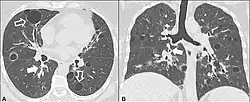

| Left lung completely affected by bullae shown in contrast to a normal lung on the right. | |

In the lungs, emphysema involves enlargement of the distal airspaces,[2] and is a major feature of chronic obstructive pulmonary disease (COPD). Other pneumatoses in the lungs are focal (localized) blebs and bullae, pulmonary cysts and cavities.